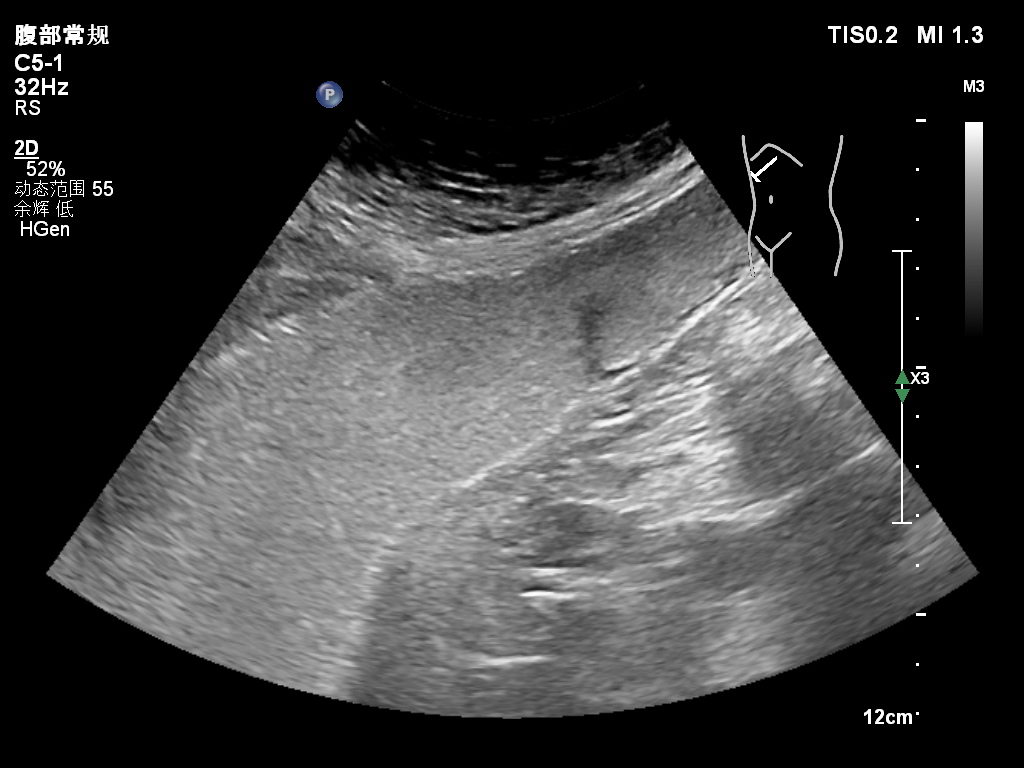

胃癌